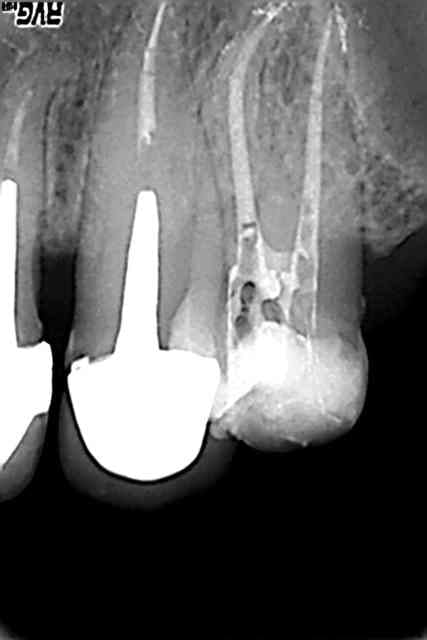

Encore une image qui laisse espérer un reconnaissance définitive de l'apport du laser tant en asepsie qu'en obturation du système endocanalaire. Merci al.